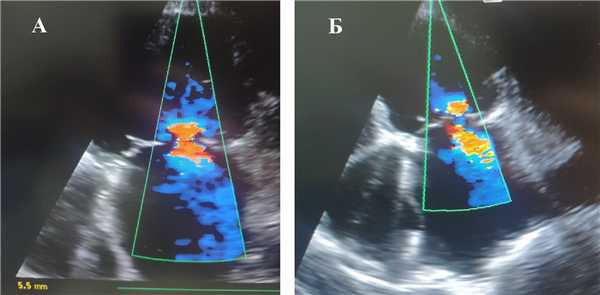

Рис. 1. Визуализация митральной недостаточности с помощью цветного допплеровского картирования до оперативного вмешательства: А — до установки внутриаортальной баллонной контрпульсации, Б — на фоне работающей внутриаортальной баллонной контрпульсации в раннем послеоперационном периоде

Результаты. В 1-ой группе на фоне применения ВАБК отмечено снижение степени МР на 58% (р